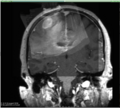

• Review data from recent AMIGO neurosurgery case (MR, US)

• Identify and evaluate sources of error

• Review options for improving overall imaging accuracy